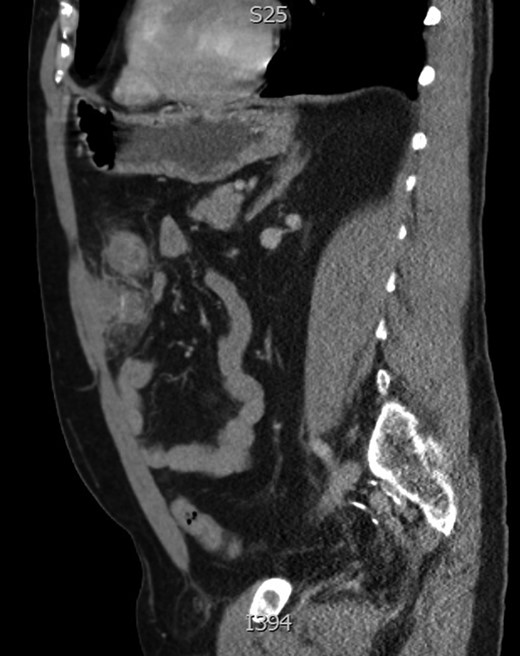

Sagittal image of anterior abdominal collection with central enhancement representing foreign body.